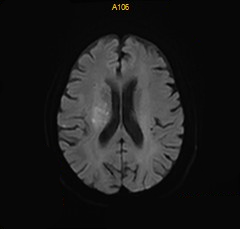

术后DWI:磁共振见少许新鲜脑梗死。

什么叫桡鞘【例久弥新】寻道于桡——瑞康通5.5F IntroSky X导管鞘经桡动脉行右侧大脑中动脉取栓一例_https://www.jmylbn.com_新闻资讯_第28张